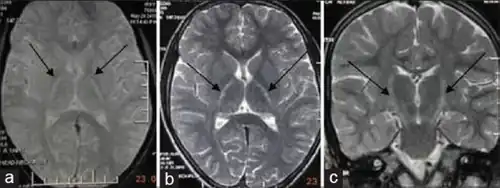

![]() | |

| An MRI with increased signal in the posterior part of the internal capsule that can be tracked to the motor cortex, consistent with the diagnosis of ALS | |